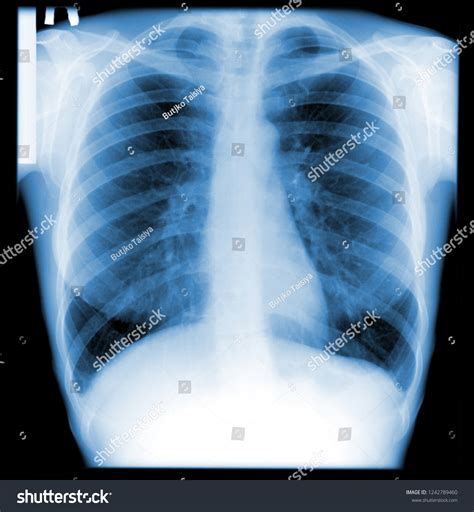

A bronchitis X ray is a crucial diagnostic tool that helps healthcare providers visualize the lungs and bronchial tubes. This imaging technique uses X-rays to create detailed images of the chest, allowing doctors to identify any abnormalities or inflammation. The bronchitis X ray can reveal:

• Inflammation and swelling of the bronchial tubes

• Presence of mucus or fluid in the lungs

• Signs of infection or pneumonia

• Structural abnormalities in the lungs

Interpreting Bronchitis X Ray Results

Interpreting the results of a bronchitis X ray requires the expertise of a radiologist or healthcare provider. The images are carefully examined for signs of inflammation, infection, or other abnormalities. Key findings that may be noted include:

• Increased density or opacity in the lungs, indicating inflammation or fluid buildup

• Thickening of the bronchial walls

• Presence of nodules or masses

• Signs of pneumonia or other respiratory infections